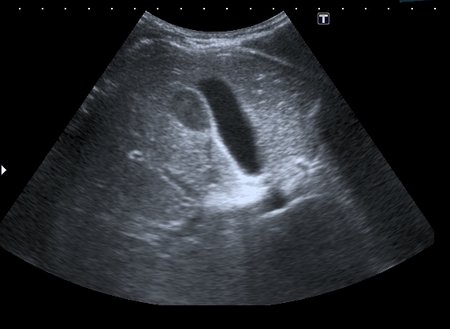

На УЗИ рядом с желчным пузырём определяется овоидное образование солидной струкутры с чёткими контурами.

При ЦДК кровоток в образовании не регистрировался, свободной жидкости в брюшной полости не было.

Порекомендовал КТ, но в связи с наступающими новогодними праздниками и каникулами мальчик уехал домой и появился повторно через 2 месяца без жалоб для контрольного исследования. На УЗИ - картина осталась без динамики

Предположил наличие удвоения желчного пузыря, с этим заключением пациент исчез из поля зрения.